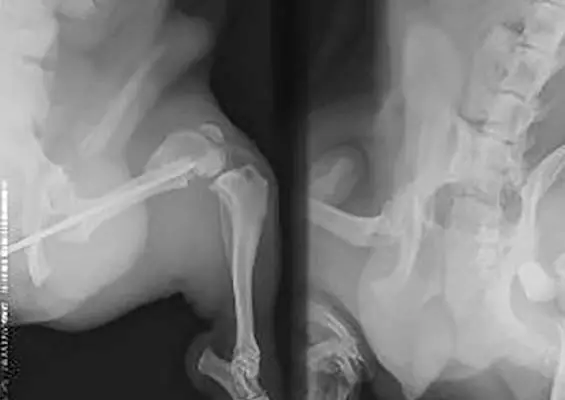

Wykorzystanie autogenicznego przeszczepu istoty gąbczastej i płyty L blokowanej w zabiegu korekcyjnym osteosyntezy kości udowej – opis przypadku